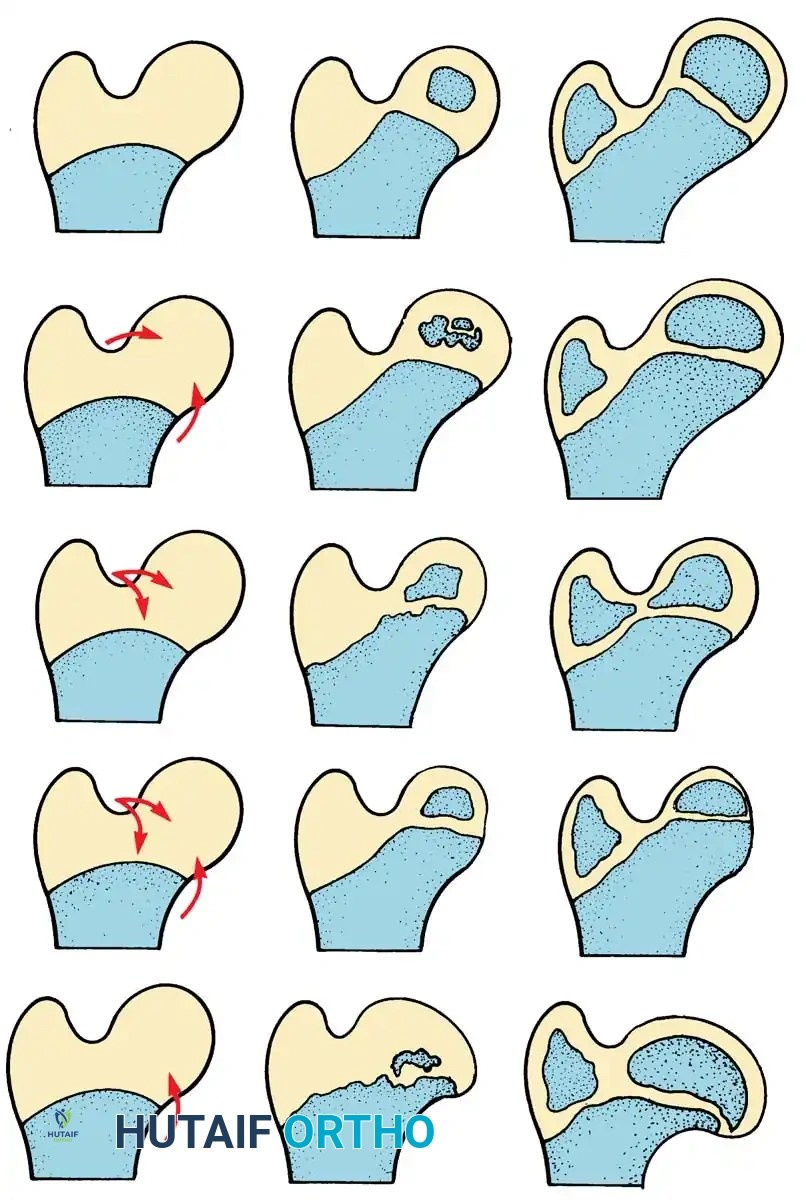

Pelvic osteotomies are broadly categorized into redirectional (e.g., Salter, Triple) and reshaping/volume-reducing (e.g., Pemberton, Dega).

- Salter Innominate Osteotomy:

- Indications: Children aged 18 months to 6 years with a congruous joint but anterolateral acetabular deficiency.

- Biomechanics: A complete transverse cut is made through the ilium just above the acetabulum to the sciatic notch. The entire acetabulum is rotated anteriorly and laterally, hinging on the pubic symphysis.

- Fixation: A triangular bone graft (harvested from the iliac crest) is placed in the osteotomy site, and the construct is stabilized with threaded Kirschner wires.

Diagrammatic representation of the Salter Innominate Osteotomy. Note the complete iliac cut and the placement of the triangular bone graft to redirect the acetabulum.

- Pemberton Pericapsular Osteotomy:

- Indications: Severe dysplasia with a capacious acetabulum.

- Biomechanics: An incomplete cut is made through the ilium, curving down to the triradiate cartilage, which acts as a hinge. This reshapes the acetabular roof, reducing its volume and improving anterolateral coverage.